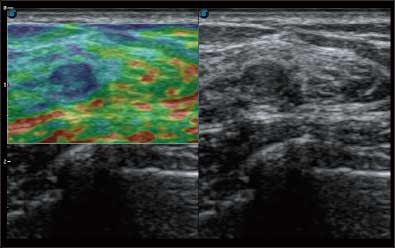

• 弹性成像

全新算法处理射频信号 不可靠区域自动剔除 支持定量分析 压力曲线保证重复性